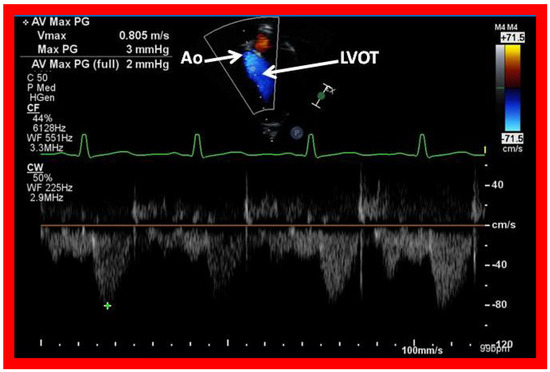

Figure 42. Selected video frames from an apical view demonstrating laminar flow from the left ventricle into the aorta (Ao). Note laminar flow in the LV outflow tract (LVOT) and low Doppler flow velocity (~0.8 m/s).

Applsci 11 09472 g042

The LA is usually normal in size (Figure 38, Figure 39 and Figure 40) and empties into the LV; laminar flow across the mitral valve (Figure 41A) can be seen. Drainage of all four pulmonary veins into the LA may be demonstrated by color flow mapping in multiple echocardiographic views. The LV is either normal in size or slightly dilated. In type I patients with normally related great arteries, the LV outflow into the aorta is demonstrable on echo-Doppler with laminar, unobstructed flow with near normal (~1.0 m/s) Doppler flow velocity (Figure 41B and Figure 42). The RV is small and hypoplastic (Figure 39 and Figure 40). If the VSD has already spontaneously closed (Figure 40), the RV has no communication with any other structures since the connection with the PAs has been severed during bidirectional Glenn or Fontan procedures. If the VSD did not undergo spontaneous closure, the RV forms a cul-de-sac connection with the LV (Figure 39 and Figure 43). In Type I patients with atresia of both tricuspid and pulmonary valves (Type Ia), the hypertrophied RV may protrude into the LV outflow region (Figure 44). However, there is usually no evidence for obstruction across this region (Figure 45).